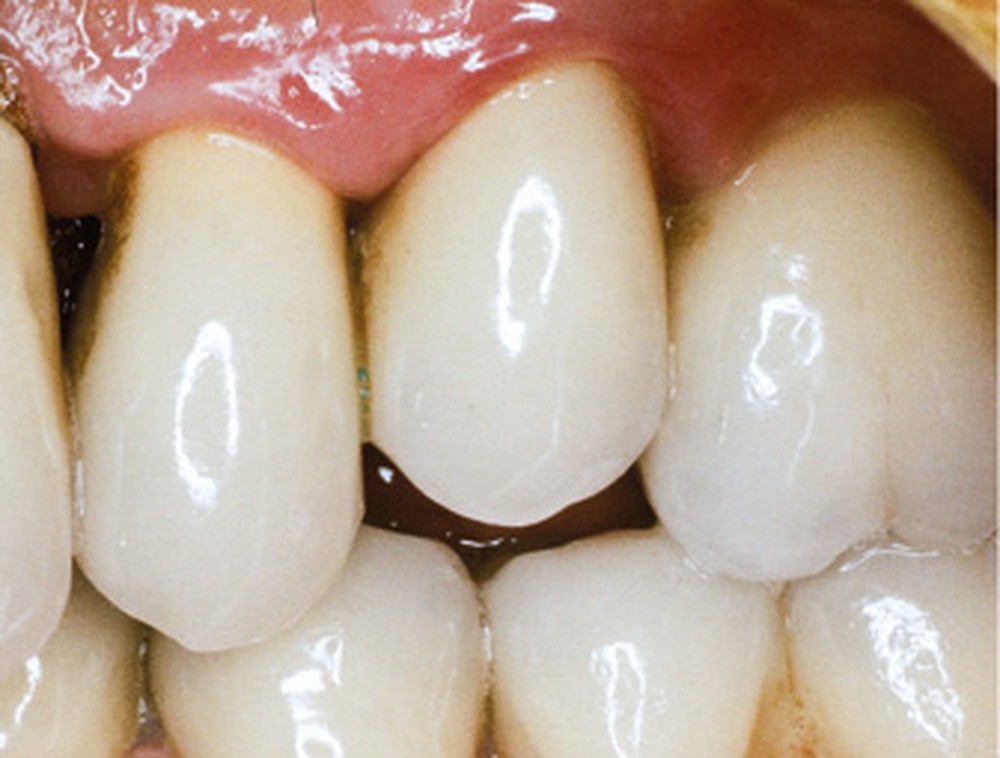

En mars 2016, la patiente se plaint d’une sensibilité sur la 25 et on note cliniquement une inflammation gingivale associée à un décalage apical du rebord marginal et de la ligne muco-gingivale en comparaison de leur situation visualisée au niveau des coiffes supra-implantaires. La couronne clinique est réduite et une infraposition avec une inocclusion d’environ 2 mm par rapport au plan d’occlusion et aux dents antagonistes est également notée (fig. 2 à 4). Un saignement au sondage ainsi qu’une poche de 5 mm en distal sont constatés. Le test de percussion est positif. Les tissus péri-implantaires adjacents ne présentent aucun signe de mucosite.

La radiographie péri-apicale au long cône confirme, sur la 25, un élargissement desmodontal, notamment en distal, des niveaux osseux mésio-distaux réduits par rapport aux clichés de contrôle précédents (les radiographies sont réalisées avec une technique parallèle avec des angulateurs de Rinn non personnalisés), un apex radiculaire normal et des niveaux osseux stables sur les implants adjacents (fig. 5). Le cisaillement systématique du fil dentaire lors de son passage confirme des points de contact très étroits entre 24, 25 et 26.